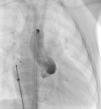

Os motivos de referência mais frequentes foram sopro e/ou cansaço. Todas as fístulas eram de origem congénita. Cinco doentes (42%) tinham patologia cardíaca concomitante: atrésia da pulmonar com septo interventricular intacto (1), canal arterial persistente (1), comunicação interauricular ostium secundum (1), estenose aórtica em válvula aórtica biscúspide (1), estenose pulmonar crítica operada no período neonatal (1). Foram realizadas angiografias selectivas para delinear a anatomia da(s) fístula(s). A embolização foi feita na porção mais distal da fístula, poupando todos os ramos colaterais. Num doente foi realizada uma ansa arteriovenosa através da fístula, com embolização da porção terminal da fístula a partir da aurícula direita. Os doentes foram heparinizados (100 U.I./kg na criança e 5000 U.I. no adulto) e foi feito o controlo posterior através do valor de ACT. Três dos doentes apresentavam duas fístulas e os restantes comunicações fistulosas isoladas. As fístulas eram todas hemodinamicamente significativas e tinham origem no território da coronária direita (n=10), da coronária esquerda (n=3) e da circunflexa (n=2) e drenavam para o ventrículo direito (n=5), artéria pulmonar (n=6), aurícula direita (n=2), seio coronário (n=1) e ventrículo esquerdo (n=1). O material de embolização incluiu 15 coils standard em 3 doentes, 1 coil Jackson® num doente (Figuras 1–3), 27 microcoils em 11 doentes (18 microcoils simples em 7 doentes e 9 microcoils GDC em 4 doentes) e um dispositivo Amplatzer®Duct Occluder num doente (Figuras 4–7). Merece um destaque especial os microcoils GDC, simples ou complexos, que são dispositivos de libertação controlada por electrólise, o que permite que o procedimento seja reversível até à fase final da libertação, após se confirmar a boa posição do dispositivo. Num doente foi testado um plug cardíaco Amplatzer® que não foi libertado por não ser adequado à lesão.

A abordagem clássica da fístula coronária é o encerramento cirúrgico. Em 1997, Mavroudis et al apresentou uma análise sobre resultados cirúrgicos de encerramento de fístulas coronárias em 17 doentes com idades compreendidas entre as seis semanas e os 16,5 anos (idade média 5,5 anos) e tratados entre 1968 e 1996, concluindo que o encerramento cirúrgico de fístulas coronárias foi 100% eficaz e sem mortalidade naquela série, pelo que deve ser o tratamento de eleição nestas situações, devendo o encerramento percutâneo ficar reservado para apenas uma pequena população seleccionada11. Contudo, já em 1991, tinha sido descrito o encerramento percutâneo de sete fístulas coronárias em doentes com idades compreendidas entre os dois e os 67 anos (idade média de 17 anos), que decorreu com sucesso em seis das sete fístulas encerradas e sem complicações durante um tempo de seguimento de quatro meses a quatro anos12. Neste artigo, os autores chamam a atenção para a vantagem do encerramento percutâneo com a possibilidade de se evidenciarem fístulas adicionais após o encerramento da(s) fístula(s) de maiores dimensões apenas visível(is) no encerramento percutâneo. Apesar de tecnicamente mais difícil, fístulas de grandes dimensões a drenarem para a aurícula direita ou para o ventrículo direito podem ser encerradas por via venosa com dispositivos como Amplatzer®Duct Occluder ou plugs, com monitorização do posicionamento adequado do dispositivo através de injecções selectivas retrógradas na artéria coronária, como descrito em 2000 por Pedra et al5 e realizado no nosso caso 9 (Fig. 1 a 4).